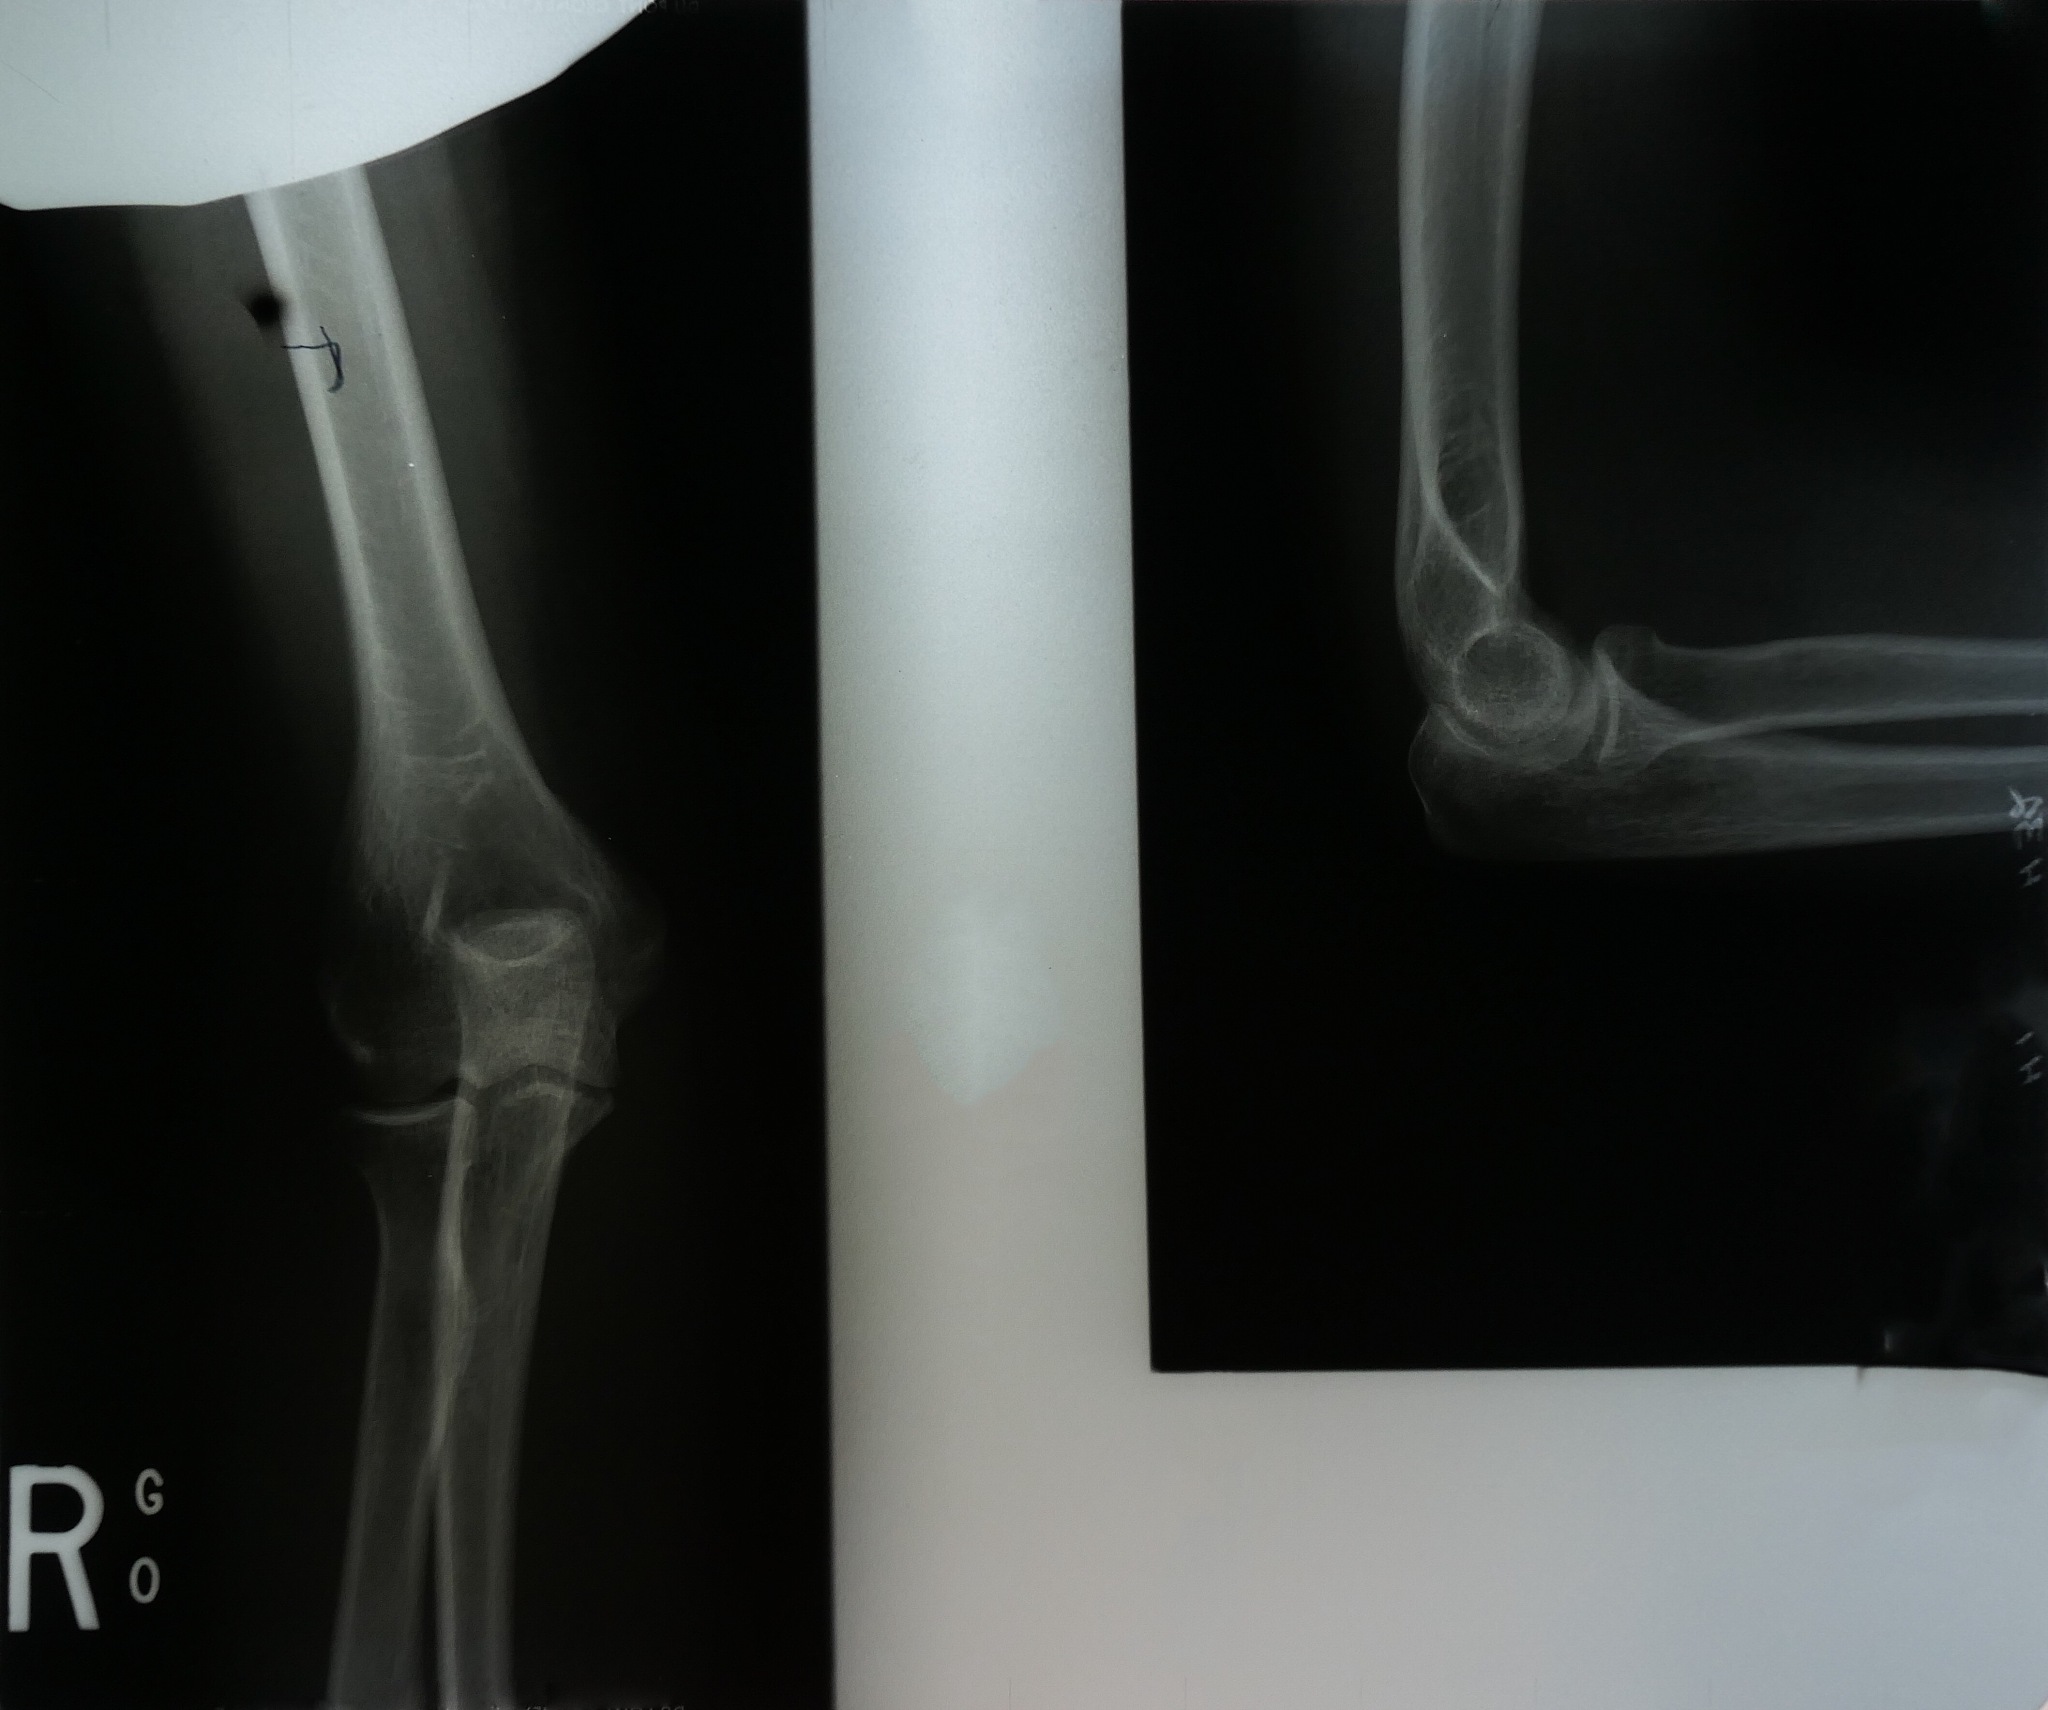

需要进行手术治疗。手术过程中,医生会使用C臂X光透视来观察骨折复位情况和钢板螺钉置入情况。C臂X光透视可以提供实时的影像,帮助医生准确定位和调整骨折的位置,确保骨折正确复位。同时,医生还可以通过C臂X光透视来指导钢板和螺钉的置入,确保它们正确安放在骨折处,以稳定骨折并促进骨折的愈合。这样可以提高手术的准确性和安全性,减少手术时间和创伤,提高手术成功率。